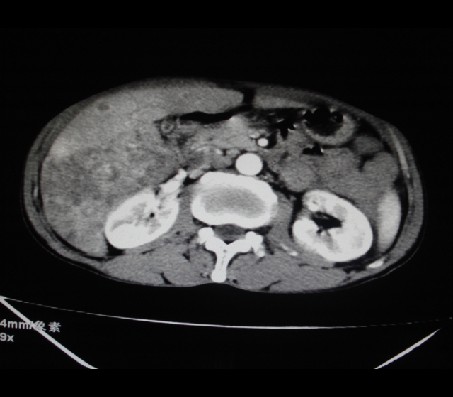

标题: CT24041:肝脏占位,请会诊!

男性,62岁。肝右叶占位,平扫及增强如下,延迟期为15分钟扫描。